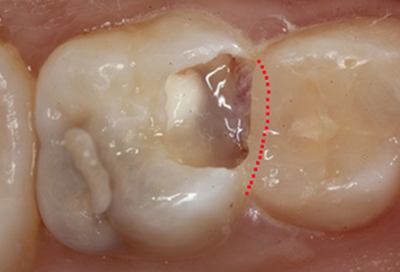

穴のあいた乳歯

乳歯の大きな役割の1つに、永久歯が出てくるまでの「場所取り」があります。

表面からパッと見て分かる穴が開くまで放置すると、乳歯の幅が小さくなるので永久歯の生える場所がなくなり、永久歯の歯ならびが悪くなってしまうのです。

永久歯の歯ならびで悩むことがないように、乳歯の虫歯は早く治すことがとても大切です。